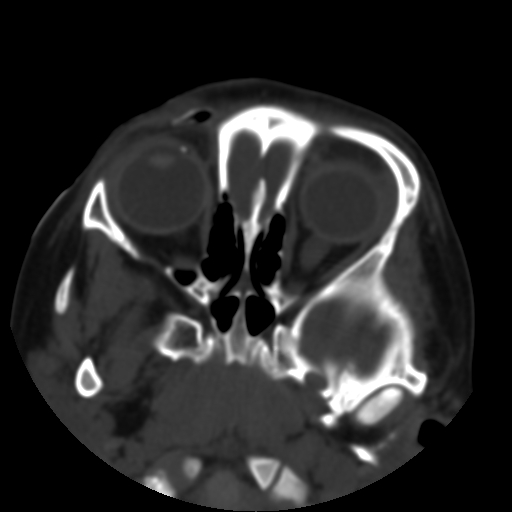

以下是引用深泽交通医院在2009-10-16 8:25:00的发言:[br]右眼环出血伴异物

以下是引用卜一在2009-10-16 15:01:00的发言:[br]右眼球挫裂伤伴异物!

以下是引用拾荒者在2009-10-17 18:38:00的发言:[br]鼻面部皮下积气,右侧睑缘及眼球壁高密度异物影,左侧眼球壁晶状体内侧缘处是圆形低密度影。低密度异物?应提请眼科医生注意。